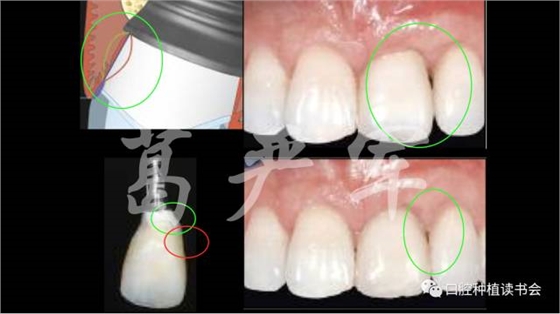

病例一,右上1缺失,在種植臨時修復期間,通過臨時冠的塑形,在正式修復后達到了比較令人滿意的治療效果。

病例二,右上12缺失,在長達半年的種植臨時修復期間,五次調整臨時修復體的穿齦外形,但幾乎沒有對粘膜邊緣的位置及右上1、2之間齦乳頭高度產生任何影響,正式修復后的美學效果也很差。

在我們了解了上述內容之后,我們再回頭看開篇筆者提到的兩個病例,這兩個病例在缺牙數(shù)目、軟硬組織缺損量、種植時機、植入的三維位置、植體規(guī)格、軟組織塑形的具體方法等諸多方面存在差異,兩個病例通過調整臨時冠穿齦輪廓進行塑形后的牙齦形態(tài)有如此大的差異也就不足為奇了。